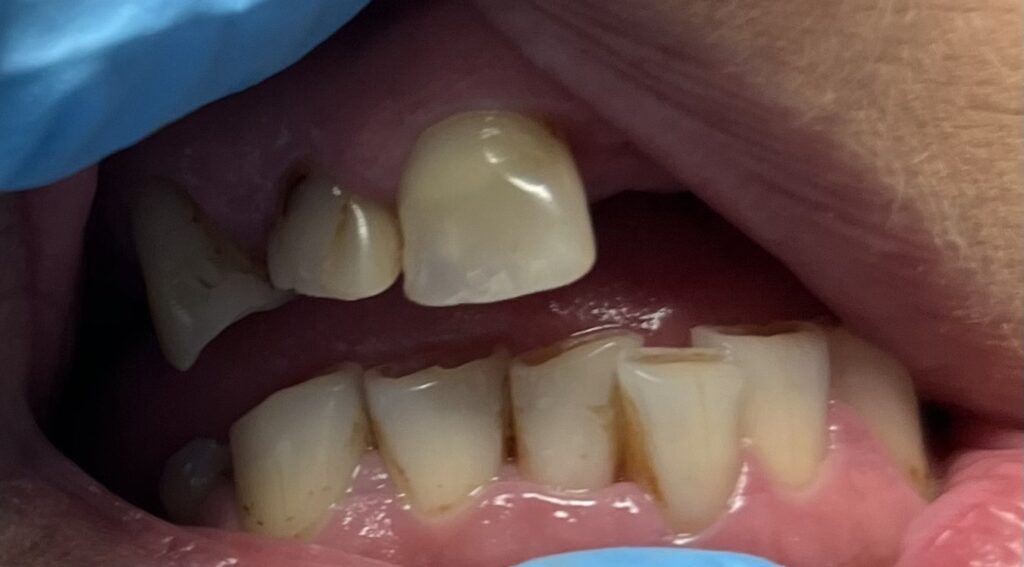

Każdy uśmiech ma swoją historię – my pomagamy ją opowiedzieć na nowo. Dzięki indywidualnie dobranym planom leczenia przywracamy pacjentom nie tylko piękny wygląd zębów, ale również komfort i funkcjonalność w codziennym życiu. Poniżej przedstawiamy wybrane przypadki metamorfoz, które pokazują, jak zaawansowana protetyka, nowoczesne techniki odbudowy oraz precyzyjne leczenie endodontyczne potrafią całkowicie odmienić uśmiech.